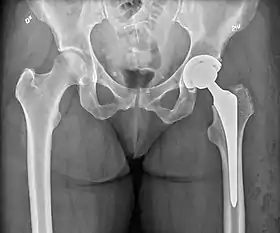

Hemiarthroplasty

Hemiarthroplasty is a surgical procedure that replaces one half of the joint with an artificial surface and leaves the other part unchanged. This class of procedure is most commonly performed on the hip after an intracapsular fracture of the femur neck (hip fracture). The procedure is performed by removing the head of the femur and replacing it with a metal or composite prosthesis. The most commonly used prosthesis designs are the Austin Moore and Thompson prostheses. A composite of metal and HDPE that forms two interphases (bipolar prosthesis) can be used. The monopolar prosthesis has not been shown to offer any advantage over bipolar designs. The procedure is recommended only for elderly/frail patients, due to their lower life expectancy and activity level. This is because over time the prosthesis tends to loosen or to erode the acetabulum.[86] Independently mobile older adults with hip fractures may benefit from a total hip replacement instead of hemiarthroplasty.[87]

Hip prosthesis for hemiarthroplasty. This example is bipolar, meaning that the head has two separate articulations.

X-ray of the hips, with a right-sided hemiarthroplasty